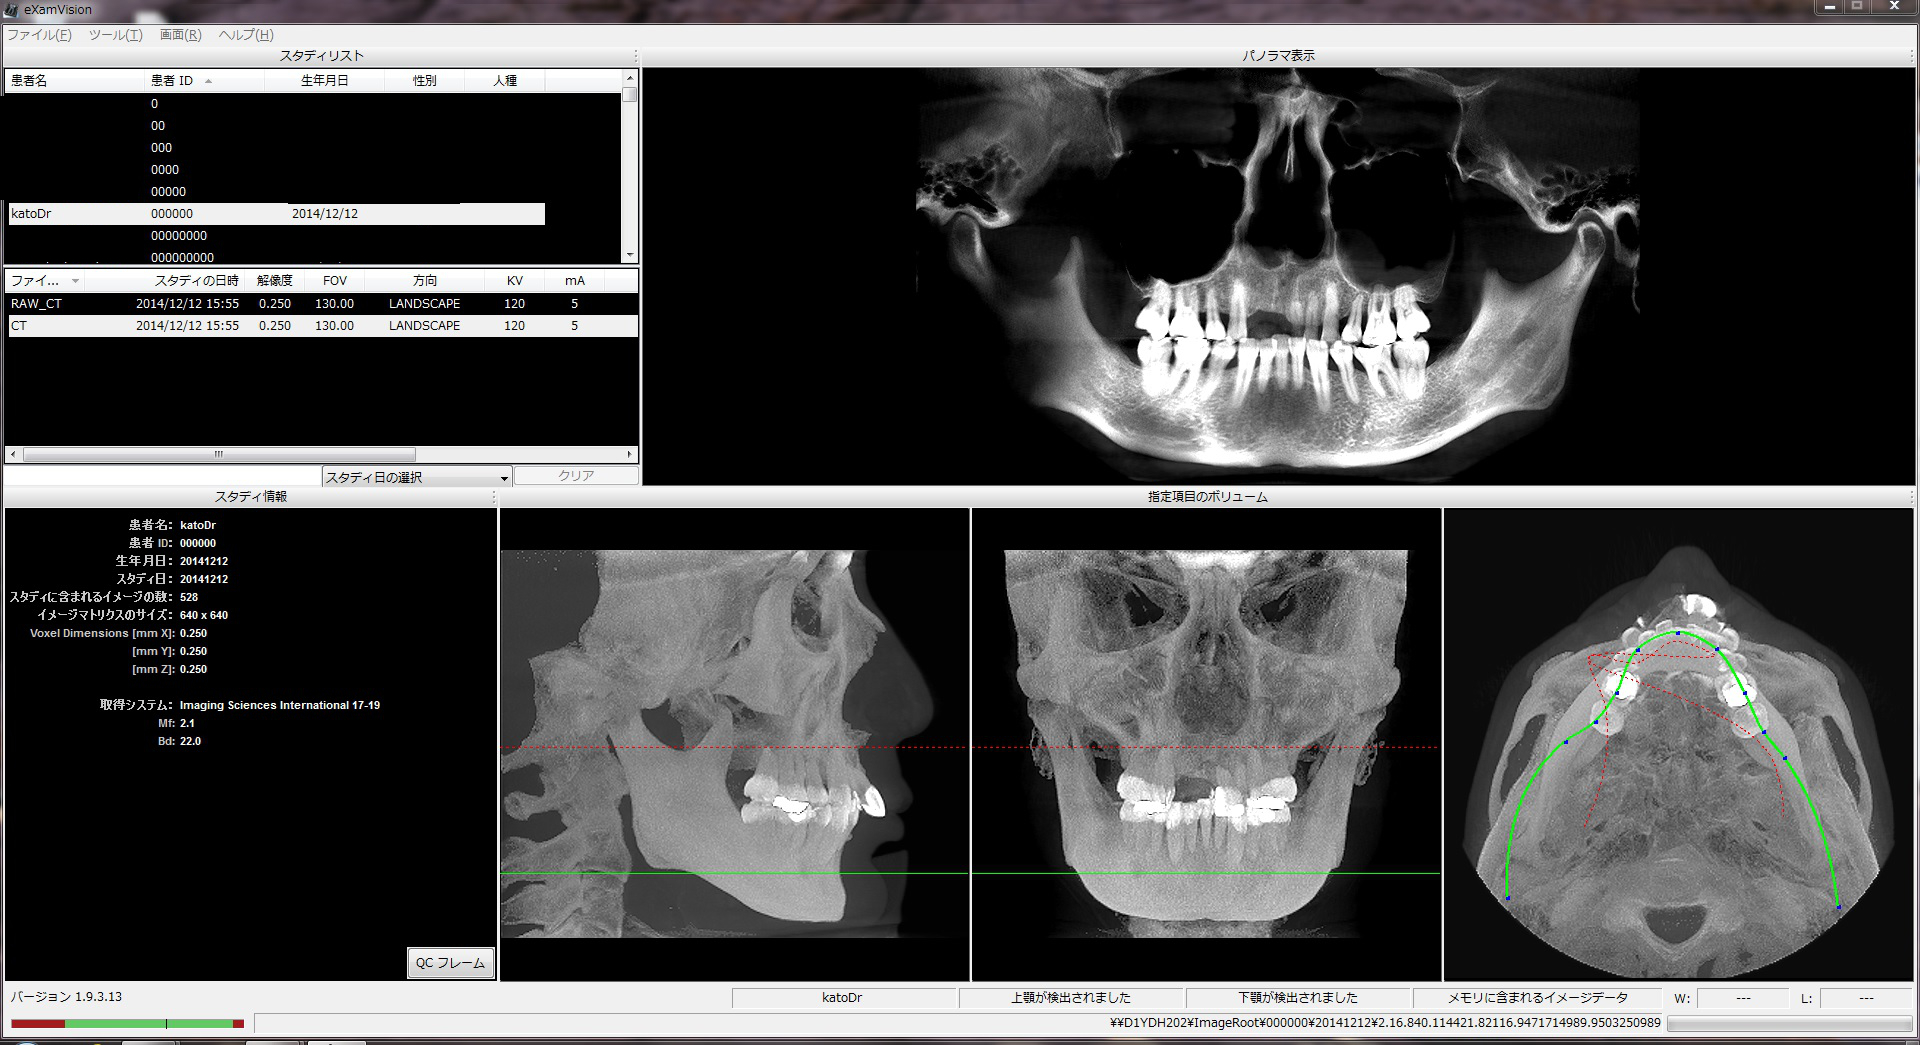

CT撮影

加藤歯科医院では最新のCT撮影機器・3D画像データ解析システムを導入し、小矯正治療時に活用しています。

A)CT画像

撮影したCTデータを編集し、セファロを表示したり、特定部位を拡大・着色したりすることができ、これらの情報をもとに診断を行います。

B)3D画像データ解析

撮影した3D画像データに矯正治療に特化した加工をします。矯正に必要な基準点をポイントすることで、顔のラインや2点間の距離および2線の角度などを計測し、精密な情報を取得します。また、顔貌を貼り付けた3D像や抜歯・矯正による歯牙の除去・移動のシミュレーション、矯正後の顔貌予測なども行えます。